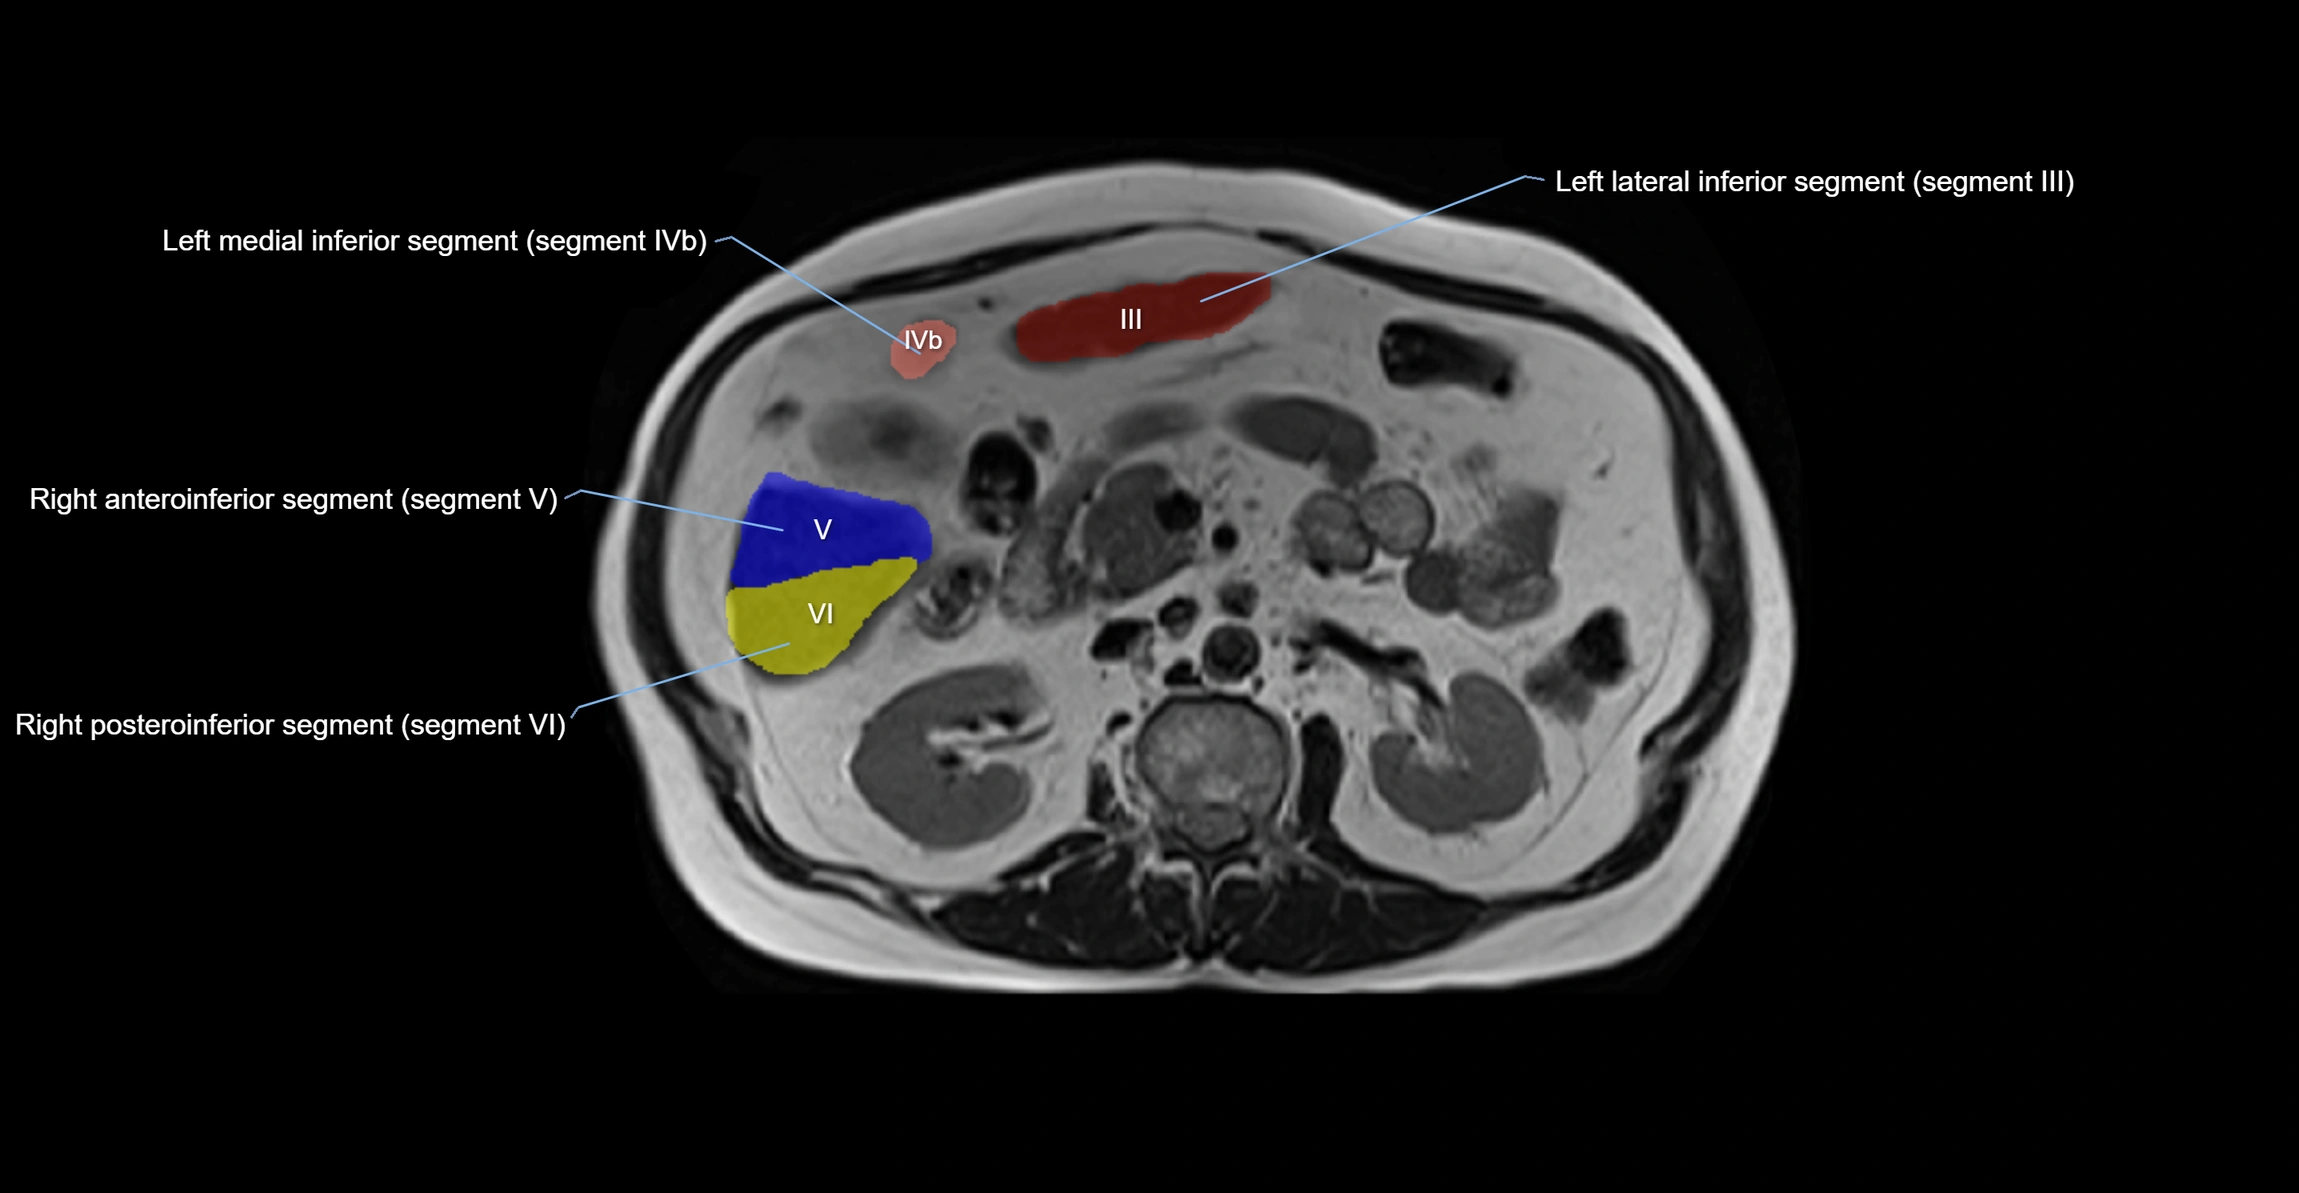

The caudate lobe of the liver is a distinct anatomical subdivision of the liver, designated as segment I in Couinaud’s classification. It lies on the posterior surface of the liver, between the fissure for the ligamentum venosum (left boundary) and the groove for the inferior vena cava (IVC) (right boundary). Superiorly, it is related to the posterior liver surface, and inferiorly it is separated from the left lobe by the porta hepatis.

The caudate lobe is unique because it receives dual portal venous and arterial inflow from both the right and left portal veins and hepatic arteries. It also has independent venous drainage directly into the IVC via multiple small hepatic veins, unlike other lobes that drain through the three main hepatic veins.

This anatomical autonomy makes the caudate lobe especially significant in liver surgery, transplantation, and hepatic venous outflow obstruction syndromes (e.g., Budd–Chiari syndrome). Enlargement of the caudate lobe is a characteristic imaging feature in chronic liver disease and cirrhosis.